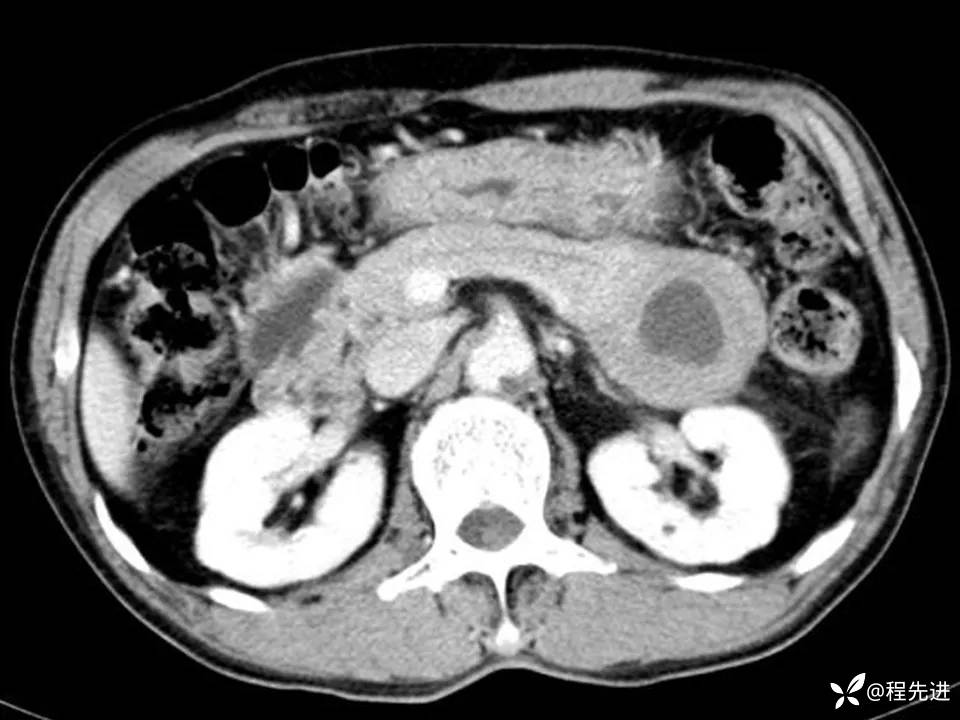

CT平扫+增强:

img